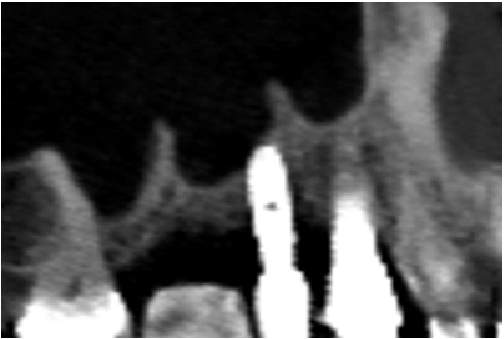

图3:手术的射线图图像

在先前描述的协议后,八名患有12例鼻窦的患者已经治疗了大型穿孔。在重新入口LASFE期间,植入物同时置于所有患者中,代表共15种植入物。愈合膜的临床评估显示出完全闭合,80%的病例中的显着增稠。虽然剩余的20%显示小的不情愿穿孔,但仍然记录膜厚度的增强。在这些病例中成功完成了Lasfe,其中延伸膜升高导致膜的塌陷,从而封闭穿孔(图3)。